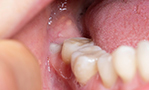

智歯周囲炎の予防 - 親知らずが半分歯肉に埋まっている場合、清掃不良により感染が起こりやすいです。

-

しかし、きちんと生えていない、横向きに生えているために掃除がしにくい、歯茎が腫れる・痛い、隣の歯が虫歯になるなど症状がある場合には抜く必要があるとお考え下さい。